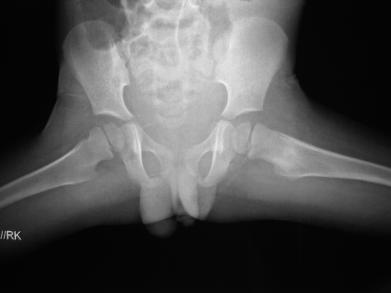

8Yr old presented with painful left sided limp & pain over left hip and thigh since 6 months. It was a boring kind of pain moderate to severe in intensity and getting relieved by Ibuprofen (NSAIDs).

X-ray showed increased bone density at the region of lesser trochanter

CT showed the typical nidus in the center of a transluscent lesion in the same region of increased density – OSTEOID OSTEOMA (Benign bony tumor)